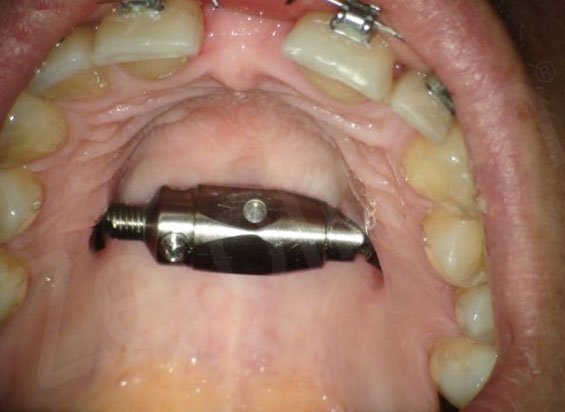

Что мне сделали на первой операции, можно посмотреть по ссылке ниже + ко всему удалили четыре зуба мудрости. Единственное, дистрактор у меня другой, крепится не на зубы, а именно к кости (примером выкладываю на фото ниже после видео, картинка из интернета, своё сфоткать пока не могу).

Мой вариант дистрактора:

Далее мне предстоит ежедневное раскручивание данного дистрактора (что будет увеличивать дальнейший разрыв тканей челюсти).